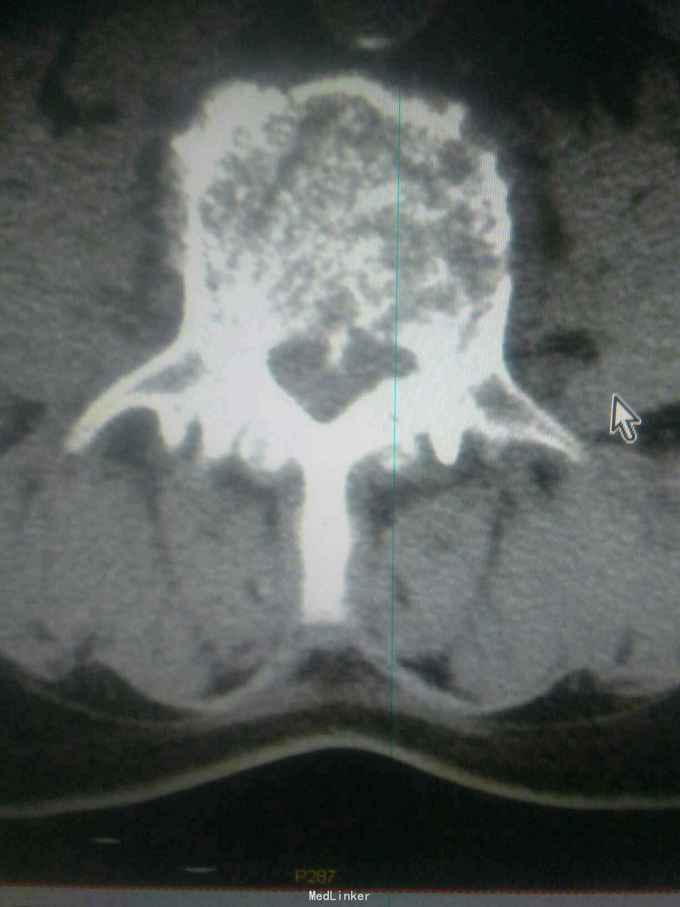

患者因高处坠落致腰痛部疼痛,双下会活动受限9小时入院。患者9小时前从3米高处坠落,腰骶部先着地,即时觉双下肢麻木,不能活动。

查体腰背部压痛,双下肢肌力0级,肌张力减低,会阴区,双下肢痛觉减低,触觉,精细觉正常,腱反射未引出,肛门反射消失,括约肌松弛。

诊断腰1,腰4椎体爆裂性骨折,腰5椎体压缩性骨折,脊髓圆锥损伤双下肢截瘫。患者入院后48小时内行了腰椎后路腰1.4椎体切开复位椎弓根钉内固定,腰1椎板切除,椎管扩大成形,横突间植骨融合术。

1.大家看看这个钉棒打得怎么样,欢迎拍砖,2.由于我院因材料没的问题有,急诊手术能力,影响脊髓损伤病人的手术疗效,,在没有内固定的前提下,一期先减压,二期上内固定,效果怎么样,请同行前辈多指导。